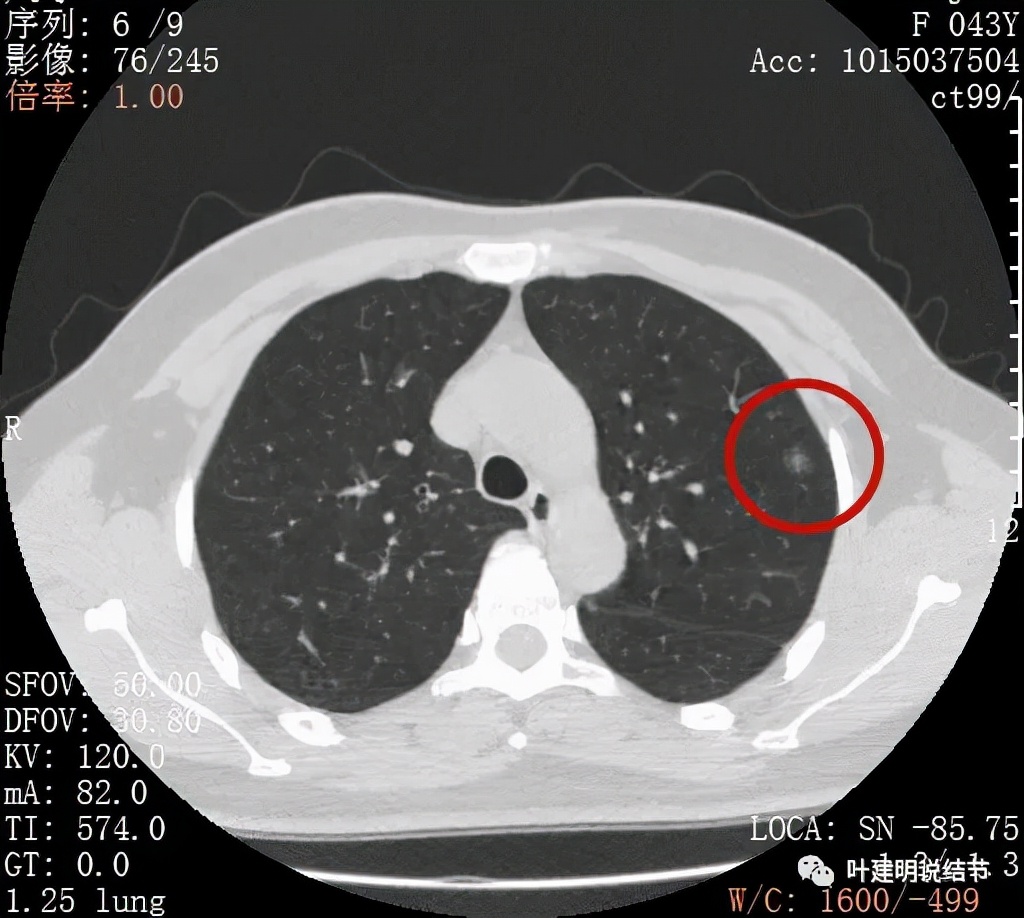

上图非常不舒服,病灶边缘有毛刺(蓝色箭头),中间有偏实性成分(粉色箭头所指),整体看密度不均杂乱

上图示明显的血管进入(桔色箭头),而且进入病灶后散大模糊,不是穿行;病灶内有高密度区域(粉色箭头)。但事后分析,绿色箭头所指的磨玻璃部分密度仍是过低,且边缘显模糊,与浸润性腺癌可能不是太符合。

以上三图均示典型的混合磨玻璃,实性成分杂乱,整体密度杂乱,并有血管征,是较为典型的浸润性腺癌影像表现。

看了后处理重建的图像,我们认为基本上应该就是浸润性腺癌了,从平扫到靶扫到靶扫描后处理,一步一步往更恶性的角度考虑。某A按我们的建议进行了单孔胸腔镜下手术,结果术中快速病理切片示:原位腺癌。我还觉得术后病理会不会升级,所以还在等石蜡切片,因为影像上,特别是后处理重建的图像太像浸润性腺癌了,结果仍是原位腺癌: